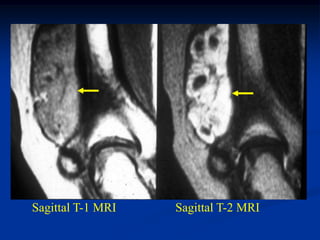

Case #1213

46 year male with

lymphangioma arm

Axial PD MRI

Another T-2 MRI

showing 2 lesions

Coronal T-2 MRI

vein

showing lymphangioma

next to cephalic vein

Sagittal T-2 MRI   vessels

showing hygroma

next to brachial

vessels